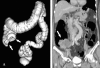

Purpose: We sought to evaluate the clinical usefulness of CT colonography (CTC) after incomplete conventional colonoscopy (CC) for occlusive colorectal cancer (CRC) according to the tumor location.

Materials and methods: Seventy-five patients with occlusive CRC underwent subsequent CTC immediately after incomplete CC. Fifty-nine patients had distal CRC and 16 had proximal colon cancer. Experienced radiologists prospectively analyzed the location, length, and TNM staging of the main tumor. The colorectal polyps in the remaining colorectum and additional extraluminal findings were also recorded. Sixty-seven patients underwent colorectal resection. We retrospectively analyzed the surgical outcome and correlated CTC and CC findings.

Results: The overall accuracies of tumor staging were: T staging, 86%; N staging (nodal positivity), 70% (80%); and intra-abdominal M staging, 94%. Additional colonic polyps were found in 23 patients. Six synchronous carcinomas were detected (9%); three in the proximal colon and three in the distal colon of occlusion. Clinically significant localization errors at CC were noted in 8 patients (12%, 5 proximal colon cancers and 3 distal CRCs) and were corrected by CTC. After CTC, the surgeons modified the initial surgical plan in 11 cases (16%).

Conclusion: In occlusive CRC, CTC is not only useful in the evaluation of the proximal bowel, but can also provide surgeons with accurate information about staging and tumor localization. CTC is recommended when endoscopists encounter occlusive CRC, regardless of tumor location.